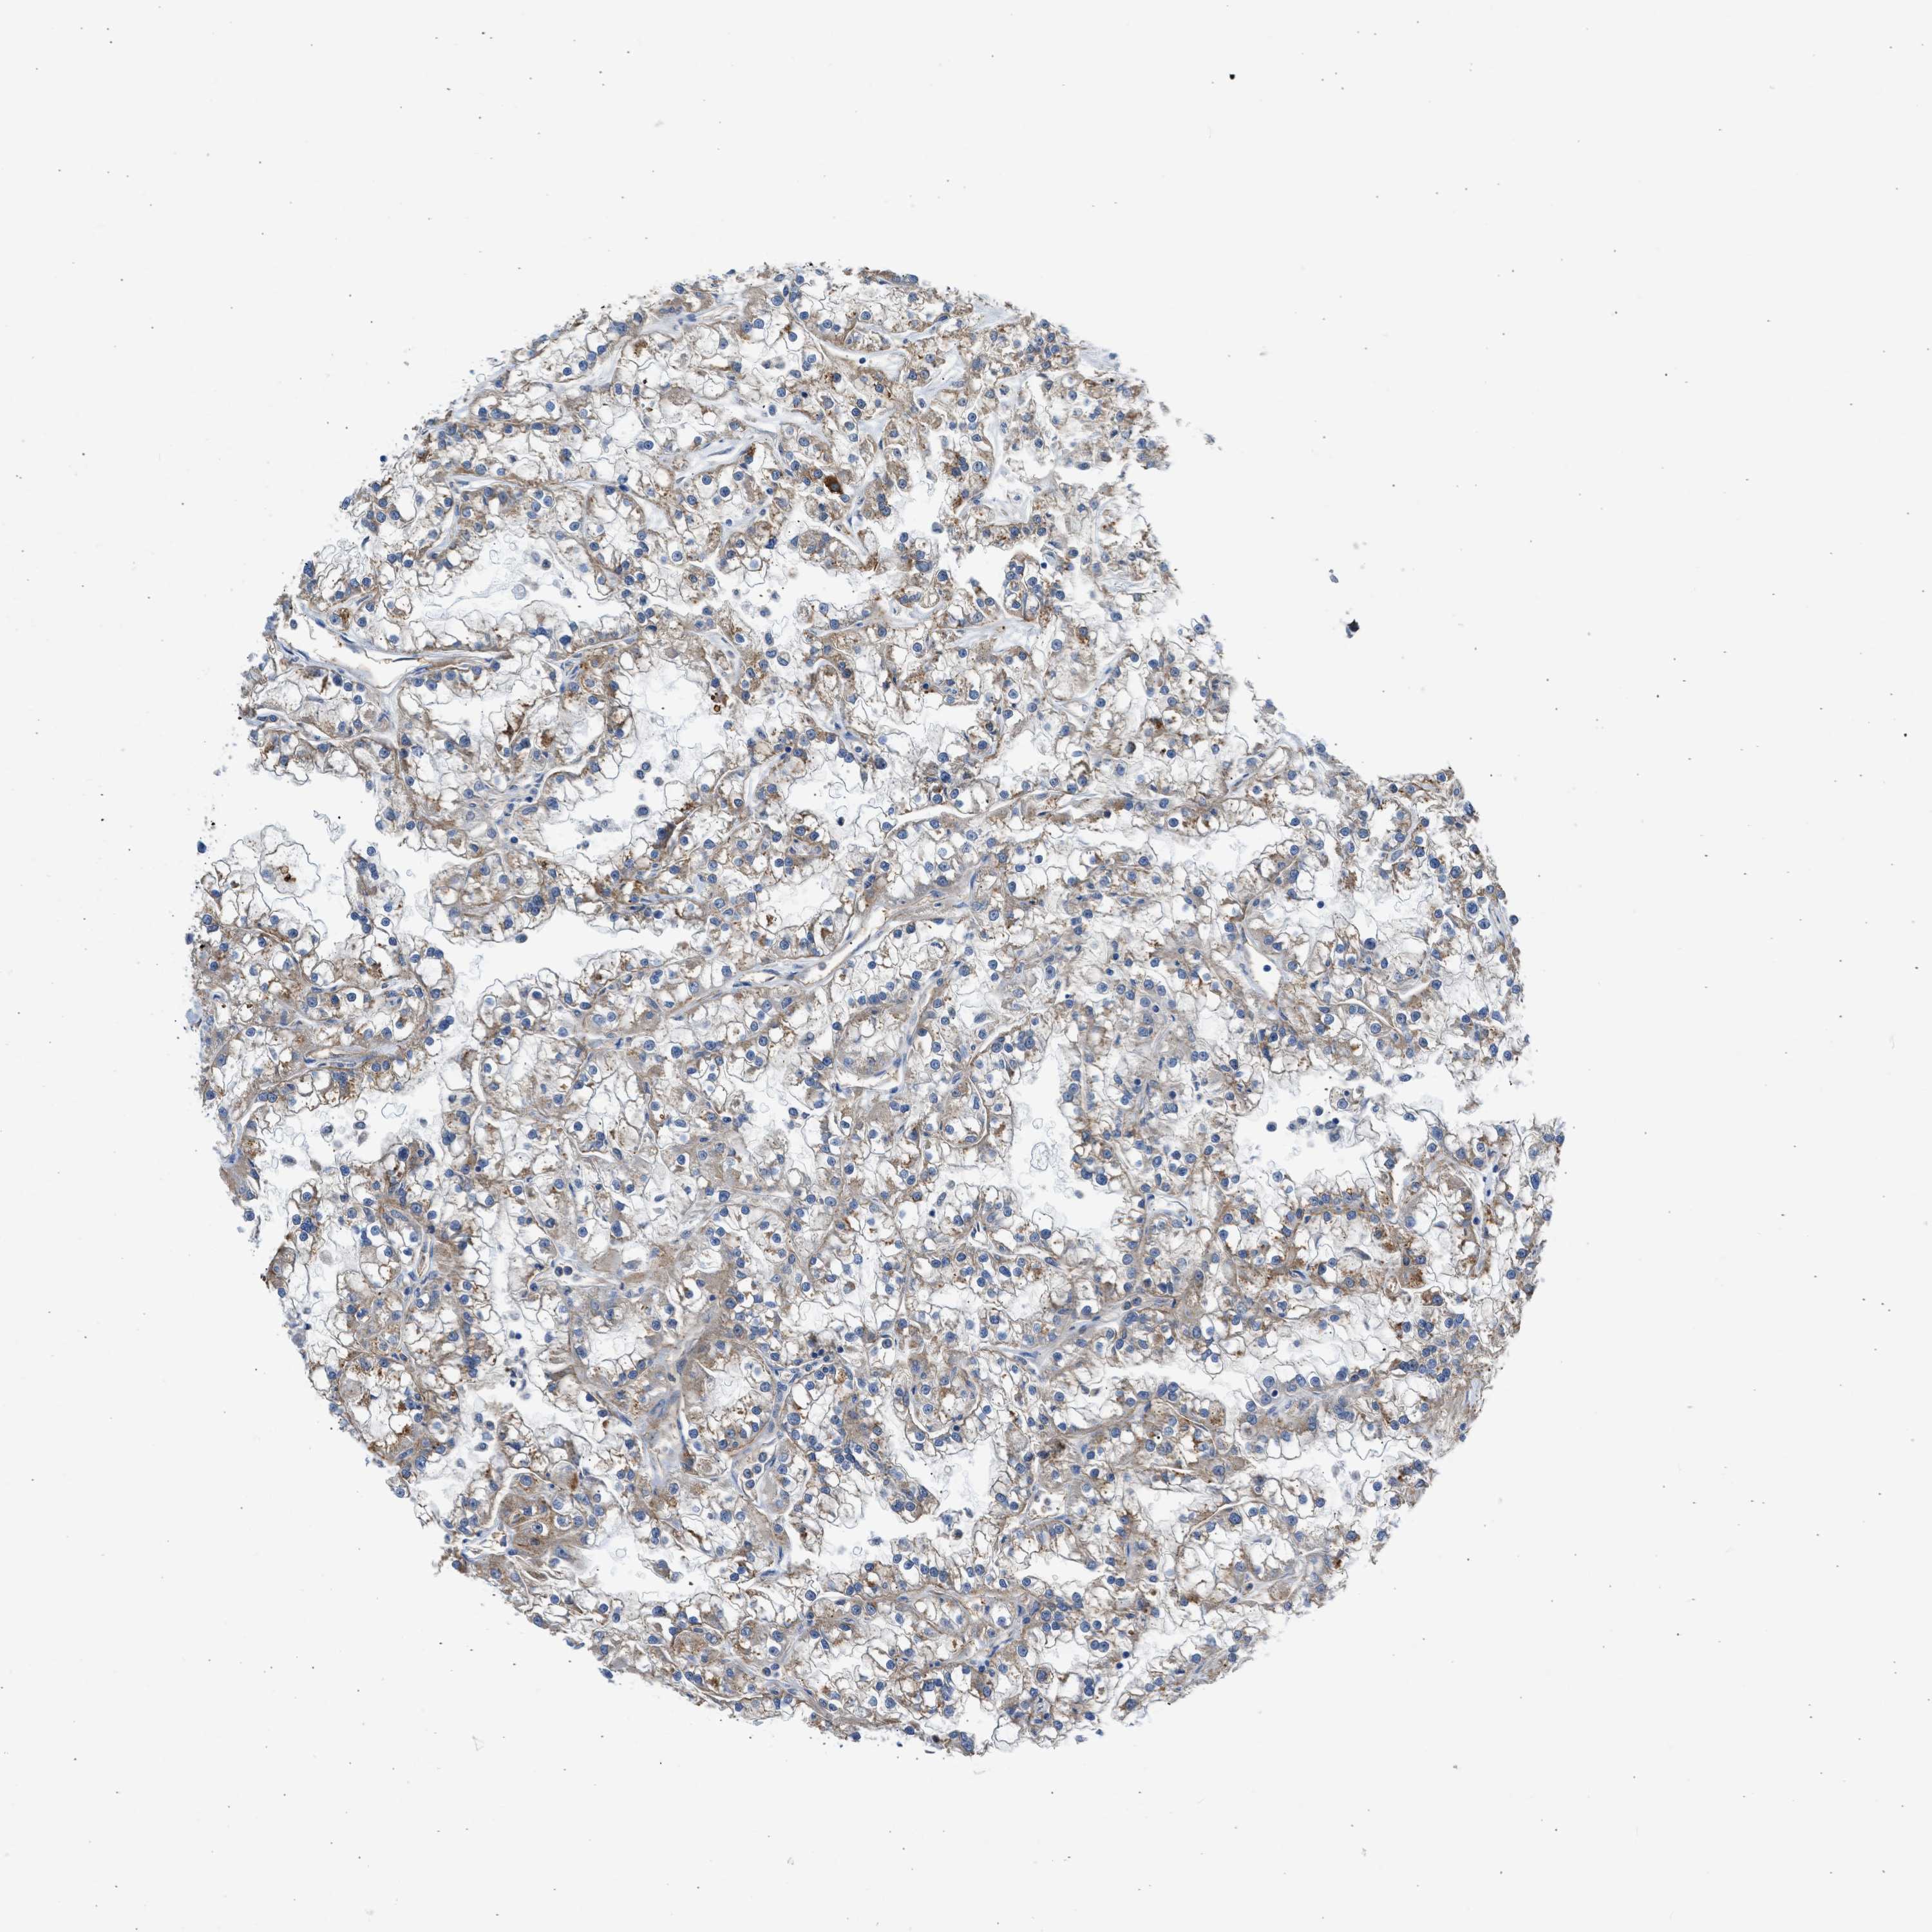

KIDNEY RENAL PAPILLARY CELL CARCINOMA (TCGA) - Interactive survival scatter ploti

The Survival Scatter plot shows the clinical status (i.e. dead or alive) for all individuals in the patient cohort, based on the same data that underlies the corresponding Kaplan-Meier plots. Patients that are alive at last time for follow-up are shown in blue and patients who have died during the study are shown in red.

The x-axis shows the expression levels (FPKM) of the investigated gene in the tumor tissue at the time of diagnosis. The y-axis shows the follow-up time after diagnosis (years). Both axes are complimented with kernel density curves demonstrating the data density over the axes. The top density plot shows the expression levels (FPKM) distribution among dead (red) and alive patients (blue). The right density plot shows the data density of the survived years of dead patients with high and low expression levels respectively, stratified using the cutoff indicated by the vertical dashed line through the Survival Scatter plot. This cutoff is automatically defined based on the FPKM cutoff that minimizes the p-score. The cutoff can be changed by dragging the vertical line or by entering a cutoff value in the square labeled "Current cut-off".

Under the Survival Scatter plot the p-score landscape (black curve; left axis) is shown together with dead median separation (red curve; right axis). Dead median separation is the difference in median mRNA expression between patients who have died with high and low expression, respectively. It is calculated as follows: median FPKM expression of dead patients with high expression - median FPKM expression of dead patients with low expression. This is intended to aid the user in visually exploring custom cutoffs and the associated p-scores and dead median separation.

Individual patient data is displayed and can be filtered by clicking on one or more of the category buttons on the top of the page. Categories describing expression level and patient information include: high, low, alive, dead, female, male and tumor stages. The scale of the x-axis can be toggled between linear and log-scale by clicking on the "x log" button. Mouse-over function shows TCGA ID, patient information and mRNA expression (FPKM) for each patient.

& Survival analysisi

Kaplan-Meier plots summarize results from analysis of correlation between mRNA expression level and patient survival. Patients were divided based on level of expression into one of the two groups "low" (under cut off) or "high" (over cut off). X-axis shows time for survival (years) and y-axis shows the probability of survival, where 1.0 corresponds to 100 percent.

ULK4 is not prognostic in Kidney Renal Papillary Cell Carcinoma (TCGA)

Best expression cut offi

: 3.18